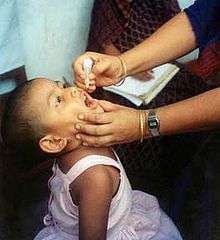

Two types of vaccine are used throughout the world to combat polio. Both types induce immunity to polio, efficiently blocking person-to-person transmission of wild poliovirus, thereby protecting both individual vaccine recipients and the wider community (so-called herd immunity).[51]

Subsequently, Albert Sabin developed another live, oral polio vaccine (OPV). It was produced by the repeated passage of the virus through nonhuman cells at subphysiological temperatures.[55] The attenuated poliovirus in the Sabin vaccine replicates very efficiently in the gut, the primary site of wild poliovirus infection and replication, but the vaccine strain is unable to replicate efficiently within nervous system tissue.[56] A single dose of Sabin's oral polio vaccine produces immunity to all three poliovirus serotypes in about 50% of recipients. Three doses of live-attenuated OPV produce protective antibody to all three poliovirus types in more than 95% of recipients.[1] Human trials of Sabin's vaccine began in 1957,[57] and in 1958 it was selected, in competition with the live vaccines of Koprowski and other researchers, by the US National Institutes of Health.[53] Licensed in 1962,[57] it rapidly became the only polio vaccine used worldwide.[53]

Because OPV is inexpensive, easy to administer, and produces excellent immunity in the intestine (which helps prevent infection with wild virus in areas where it is endemic), it has been the vaccine of choice for controlling poliomyelitis in many countries.[58] On very rare occasions (about one case per 750,000 vaccine recipients), the attenuated virus in OPV reverts into a form that can paralyze.[24] Most industrialized countries have switched to IPV, which cannot revert, either as the sole vaccine against poliomyelitis or in combination with oral polio vaccine.[59]